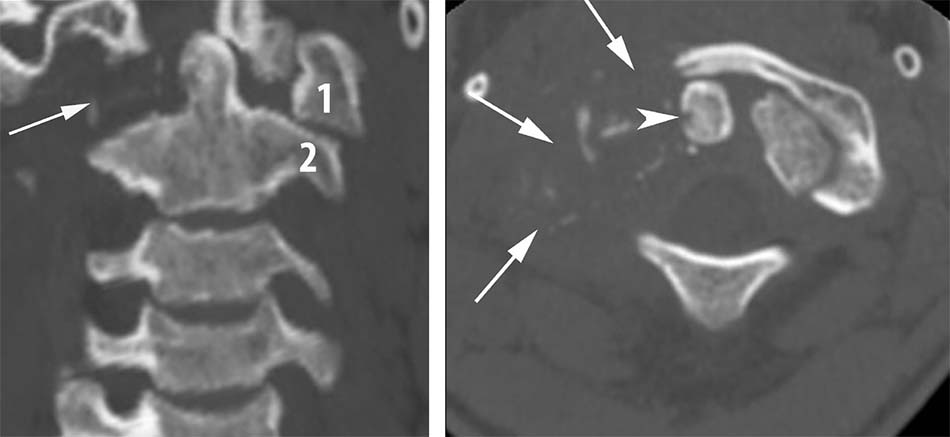

2.1.4. Gãy mỏm nha

Chiếm 10-15 % tổn thương cột sống cổ và 75% chấn thương cột sống cổ ở trẻ em, gặp ở nhiều nhóm tuổi. Cơ chế tổn thương do ép đứng dọc phối hợp với lực di lệch ngang [24],[42]. Althoff cho rằng gãy mỏm nha là hậu quả của lực ép quanh trục phối hợp lực trượt đứng thẳng [47]. Theo một nghiên cứu khác thì gãy mỏm nha di lệch ra trước gấp 7 lần di lệch ra sau. Dây chằng cũng đóng vai trò quan trọng, trong đó dây chằng cánh và dây chằng dọc trước thường phối hợp với gãy mỏm nha [27],[35]. Năm 1974, Anderson và D’Alonzo mổ tả tổn thương thành 3 loại dựa trên phân tích 60 bệnh nhân gãy mỏm nha từ năm 1964 đến 1972 [42]:

- Loại 1: Gãy chéo qua đỉnh, tổn thương vững, điều trị bảo tồn thường không để lại di chứng (gãy chỏm).

Hình 1.30. Gãy mỏm nha loại 1. - Loại 2: Gãy qua nền mỏm nha, nơi tiếp giáp giữa mỏm nha và thân C2. Là tổn thương thường gặp nhất, loại gãy này tỉ lệ khớp giả cao khoảng 65%, nguyên nhân do vùng này cấp máu kém [24]. Theo Roy – Camille, có tới 40% thuộc loại này để lại di chứng khớp giả nếu điều trị bảo tồn. Trong nhóm này, Hadley xếp những trường hợp có mảnh rời ở nền mỏm răng vào loại 2A và cho đó chính là nguyên nhân thất bại trong điều trị bảo tồn [50].

Hình 1.31. Gãy mỏm nha loại 2 - Loại 3: Đường gãy chéo qua thân C2, điều trị bảo tồn tỷ lệ liền xương cao. Năm 1974, Roy – Camille phân loại theo hướng của đường gãy giúp cho hướng phẫu thuật thích hợp: đường gãy chéo xuống, di lệch ra trước, đường gãy chéo xuống, di lệch ra sau, đường gãy ngang.

Hình 1.32. Gãy mỏm nha loại 3